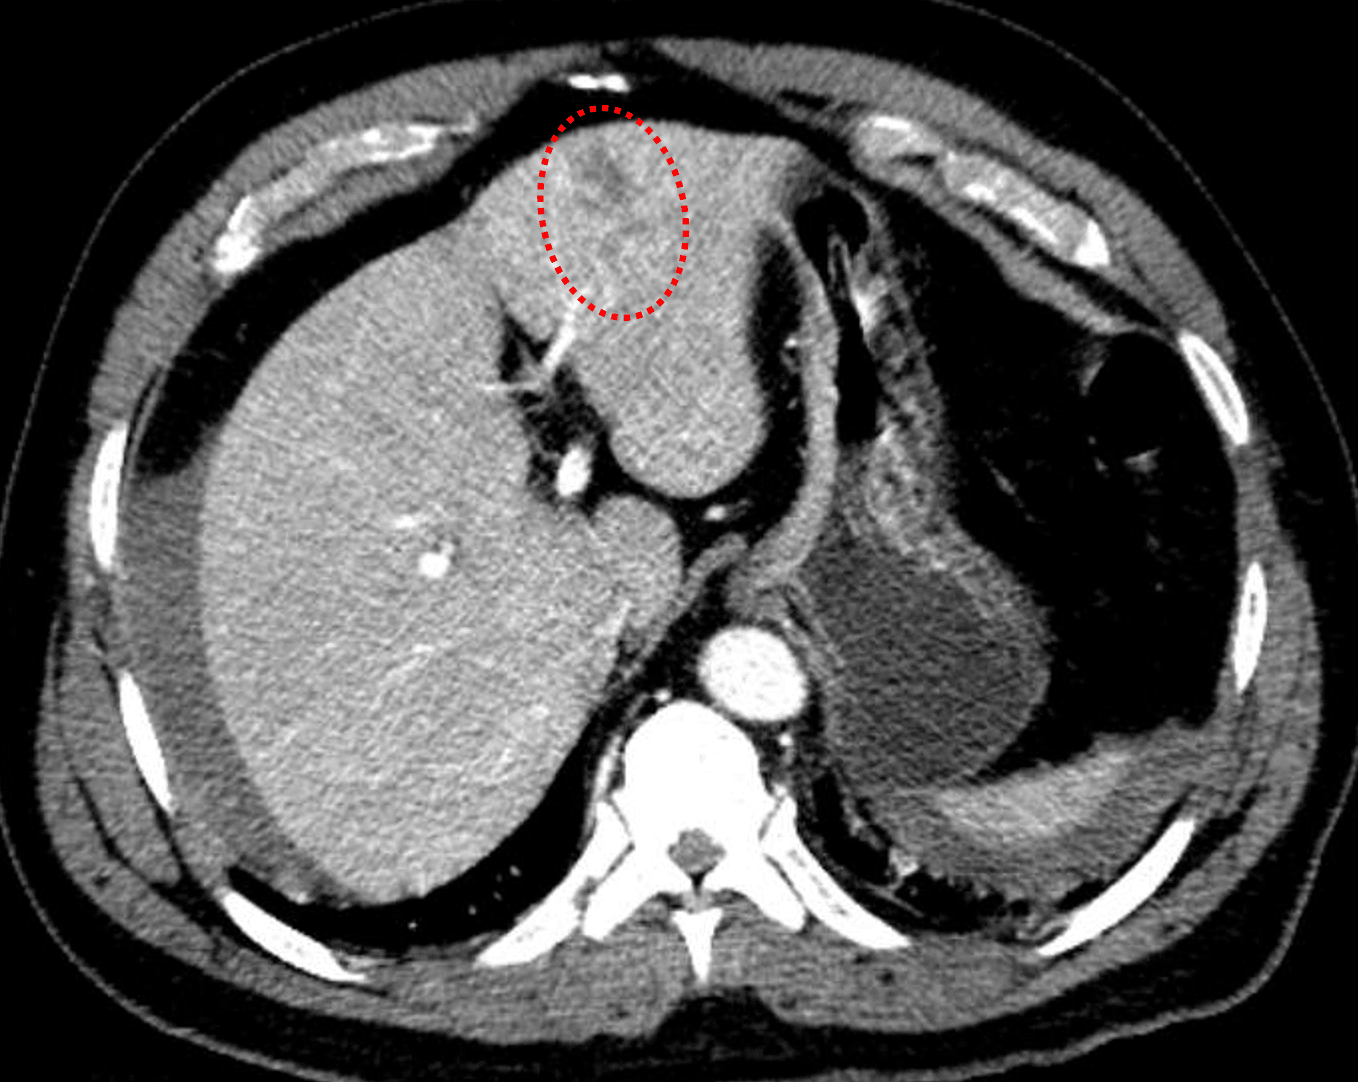

- Hepatic laceration involving segments 2/3 measuring 4.4 cm in greatest span. No extension to the hilum or evidence of active hemorrhage

Grade 3 hepatic laceration in segments 2/3 with moderate volume hemoperitoneum.

- Hepatic injuries can be classified using the AAST system, as shown in the table below. While including the classification of injuries is not always important, it is important to generate reports that will be meaningful to your referring surgeons.

- Any time you see a laceration or hematoma, make sure to compare closely between arterial and delayed phases for signs of arterial injury including hemorrhage (should get larger and less poorly defined on delayed phase) and pseudoaneurysm (should remain similar in appearance on delayed phase)

Red outline: hepatic laceration in segment 4 measuring greater than 3 cm in depth.